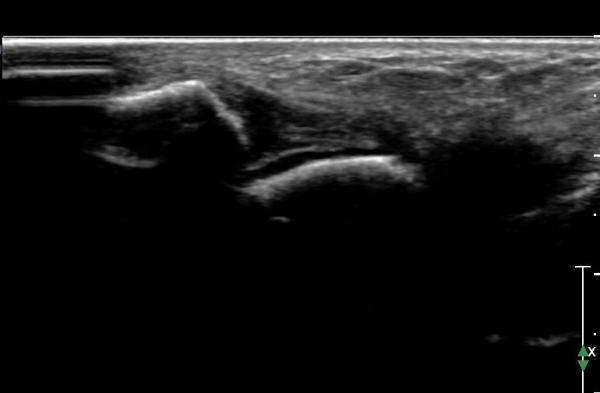

ÇϺΠ½ÅÀü ¶ì(inferior extensor retinaculum) ÀÇ frondiform Àδë Á¾´Ü¸é°Ë»ç¿¡¼­

frondiformÀÎ´ë ½ÉºÎ°¡Áö ÁÖº¯ ¼ö¾×Àú·ù°¡ °üÂûµÇ°í Á·±Ùµ¿ °æºÎÀδ밡 ³Ê¹« ¶Ñ·ÇÈ÷

°üÂûµÈ´Ù(»çÁø 5, 6, 7).